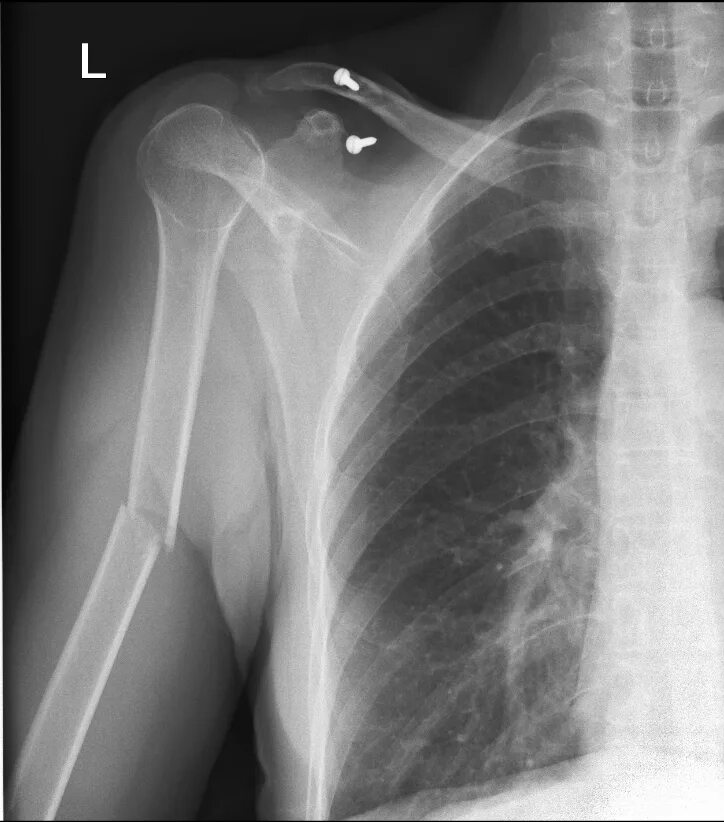

Сколько срастается плечевой перелом